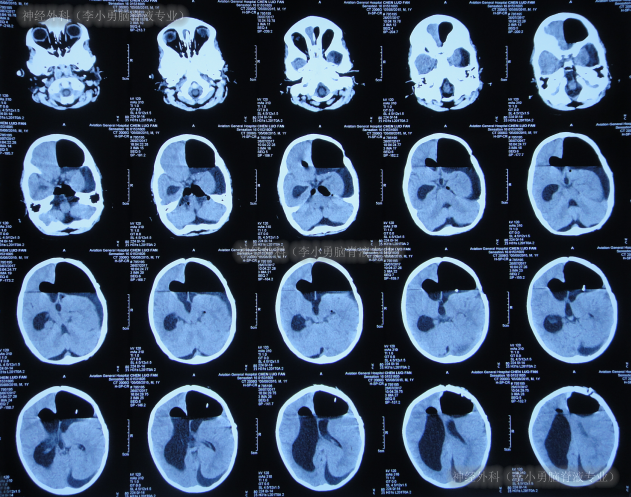

患儿于出生后10月龄即2016年6月1日,患儿意外摔伤头部,在当地的福建省福州市某医院,查头颅CT(图-1)后给予保守治疗后出院观察。

图-1:2016年6月1日头颅CT